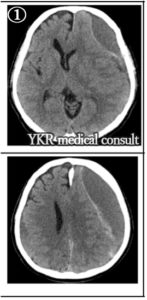

①事故後約3か月:病状悪化により受診した際のもので、両側の慢性硬膜下血腫を認め、左側には多量に血腫が貯溜し強く脳を圧迫している。